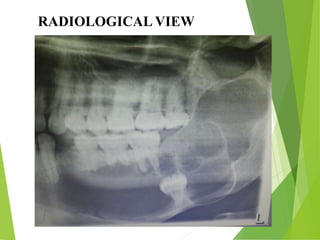

RADIOLOGICAL VIEW

RADIOGRAPHIC FINDINGS

• Ameloblastomas are osteolytic & present as

unilocular or multilocular.

• Well circumscribed by bony radiopaque borders

• Margins are usually well defined & sclerotic

• Root resorption & tooth displacement.

• Displacement of the neurovascular bundle

• Cortex shows thinning and often severe expansion

• Involvement of the antrum is seen as an opacification.